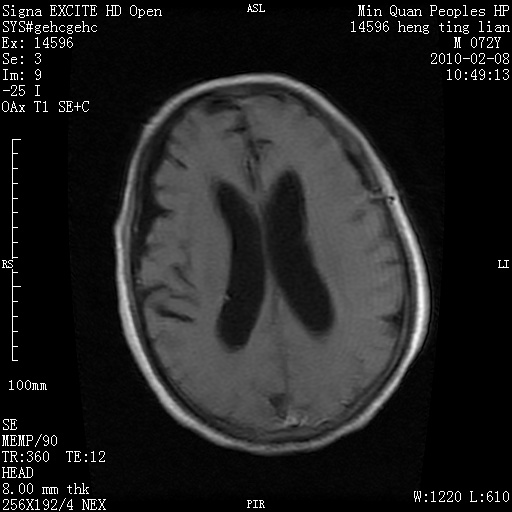

m,72,头疼,头晕两年,伴视力模糊三月,饮食呛咳两天。pe:颈部抵抗,左眼突出,左眼瞳孔约3mm,对光反射消失,双眼失明,伸舌困难,双肺呼吸音粗,心率110次/分,左上肢肌力i级,左下肢屈曲,肌张力高。现有08年2月19mri平扫及10年2月8日mri增强请会诊。ct病灶呈低密度伴散在点、片状等密度区,无明确钙化(无ct片资料可供上传)。[

左侧桥小脑区占位伴梗阻性脑积水----考虑 1神经鞘瘤 2室管膜瘤。

左侧桥小脑区神经鞘瘤伴梗阻性脑积水。

左侧桥脑小脑角区肿瘤并脑积水,考虑听神经瘤,脑膜瘤?

左侧桥脑小脑角区肿瘤并脑积水,考虑听神经瘤,